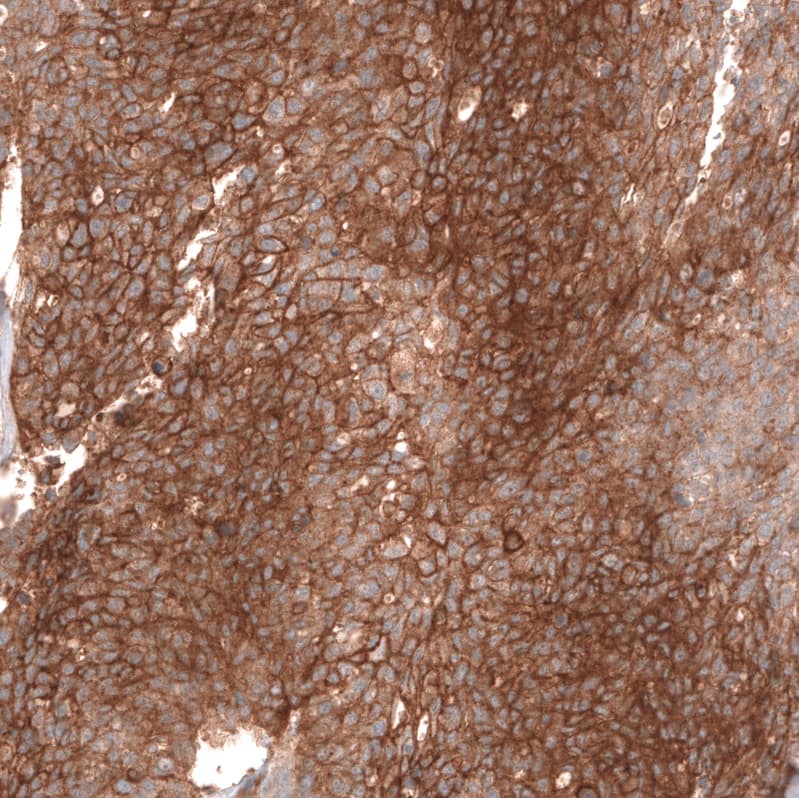

FXYD5/Dysadherin Antibody (CL14037) - Azide and BSA Free Immunohistochemistry-Paraffin: FXYD5/Dysadherin Antibody [NBP3-43835]

Immunohistochemistry-Paraffin: FXYD5/Dysadherin Antibody [NBP3-43835]

Staining of human breast cancer shows strong membranous positivity in tumor cells.